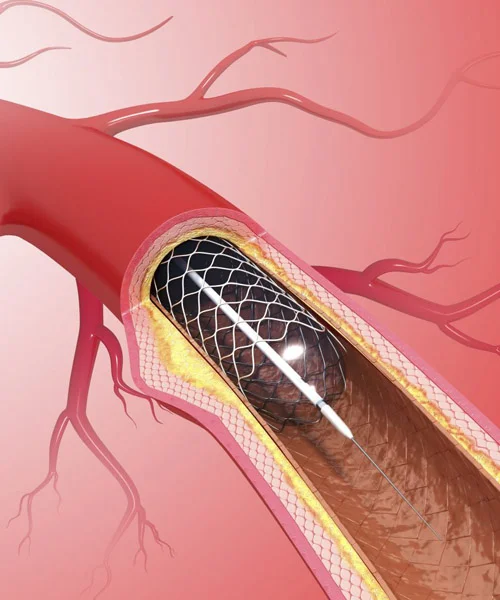

He holds prestigious qualifications including MBBS, MD in General Medicine, and DM in Cardiology, making him a highly skilled expert in interventional cardiology. Dr. Yogesh Nagendra has extensive expertise in procedures such as angiography, angioplasty, pacemaker implantation, Balloon Mitral Valvotomy (BMV), ECHO, and TMT, ensuring accurate diagnosis and effective treatment for every patient.